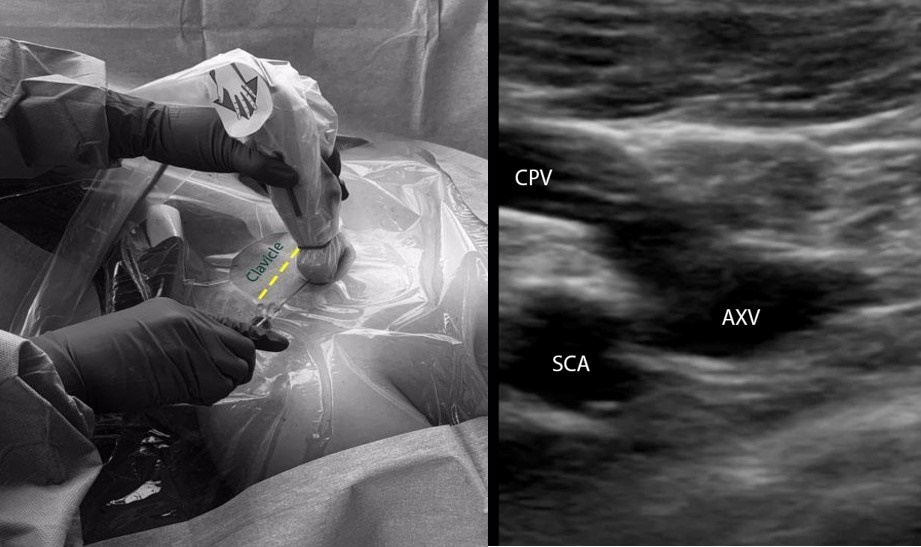

A. Infraclavicular in-plane approach (Figure 2):

- Position the patient in the supine or Trendelenburg position. The patient should be prepped and draped in the usual sterile fashion. The ipsilateral IJV and the contralateral SCV areas should also be prepped and draped.

- Place a linear transducer (6-13 MHz) in the infraclavicular fossa, approximately 2-3 cm distal to where the SCV courses below the clavicle.

- Obtain a long-axis view of the axillary vein and the distal SCV. Evaluate the depth, caliber, and patency of the axillary vein and the SCV.

- Use compressibility and/or pulse-wave Doppler to confirm that the structure visualized is indeed the vein, and not the artery.

- Insert the needle in the midpoint of the small footprint transducer using the in-plane approach. The needle should be advanced slowly, taking note of the lung pleura underneath the vessels.

- If needle visualization is lost, it is important to stop advancing the needle. Withdraw slightly and re-visualize the needle before proceeding.

- Once within the lumen of the vessel, insert the guidewire and monitor the guidewire placement in real time with ultrasound.

- Make a small incision on the skin, dilate the vessel, and insert the catheter over the guidewire.

Figure 2: Ultrasound-guided subclavian vein cannulation. AXV (axillary vein), SCA (subclavian artery), SCV (subclavian vein).